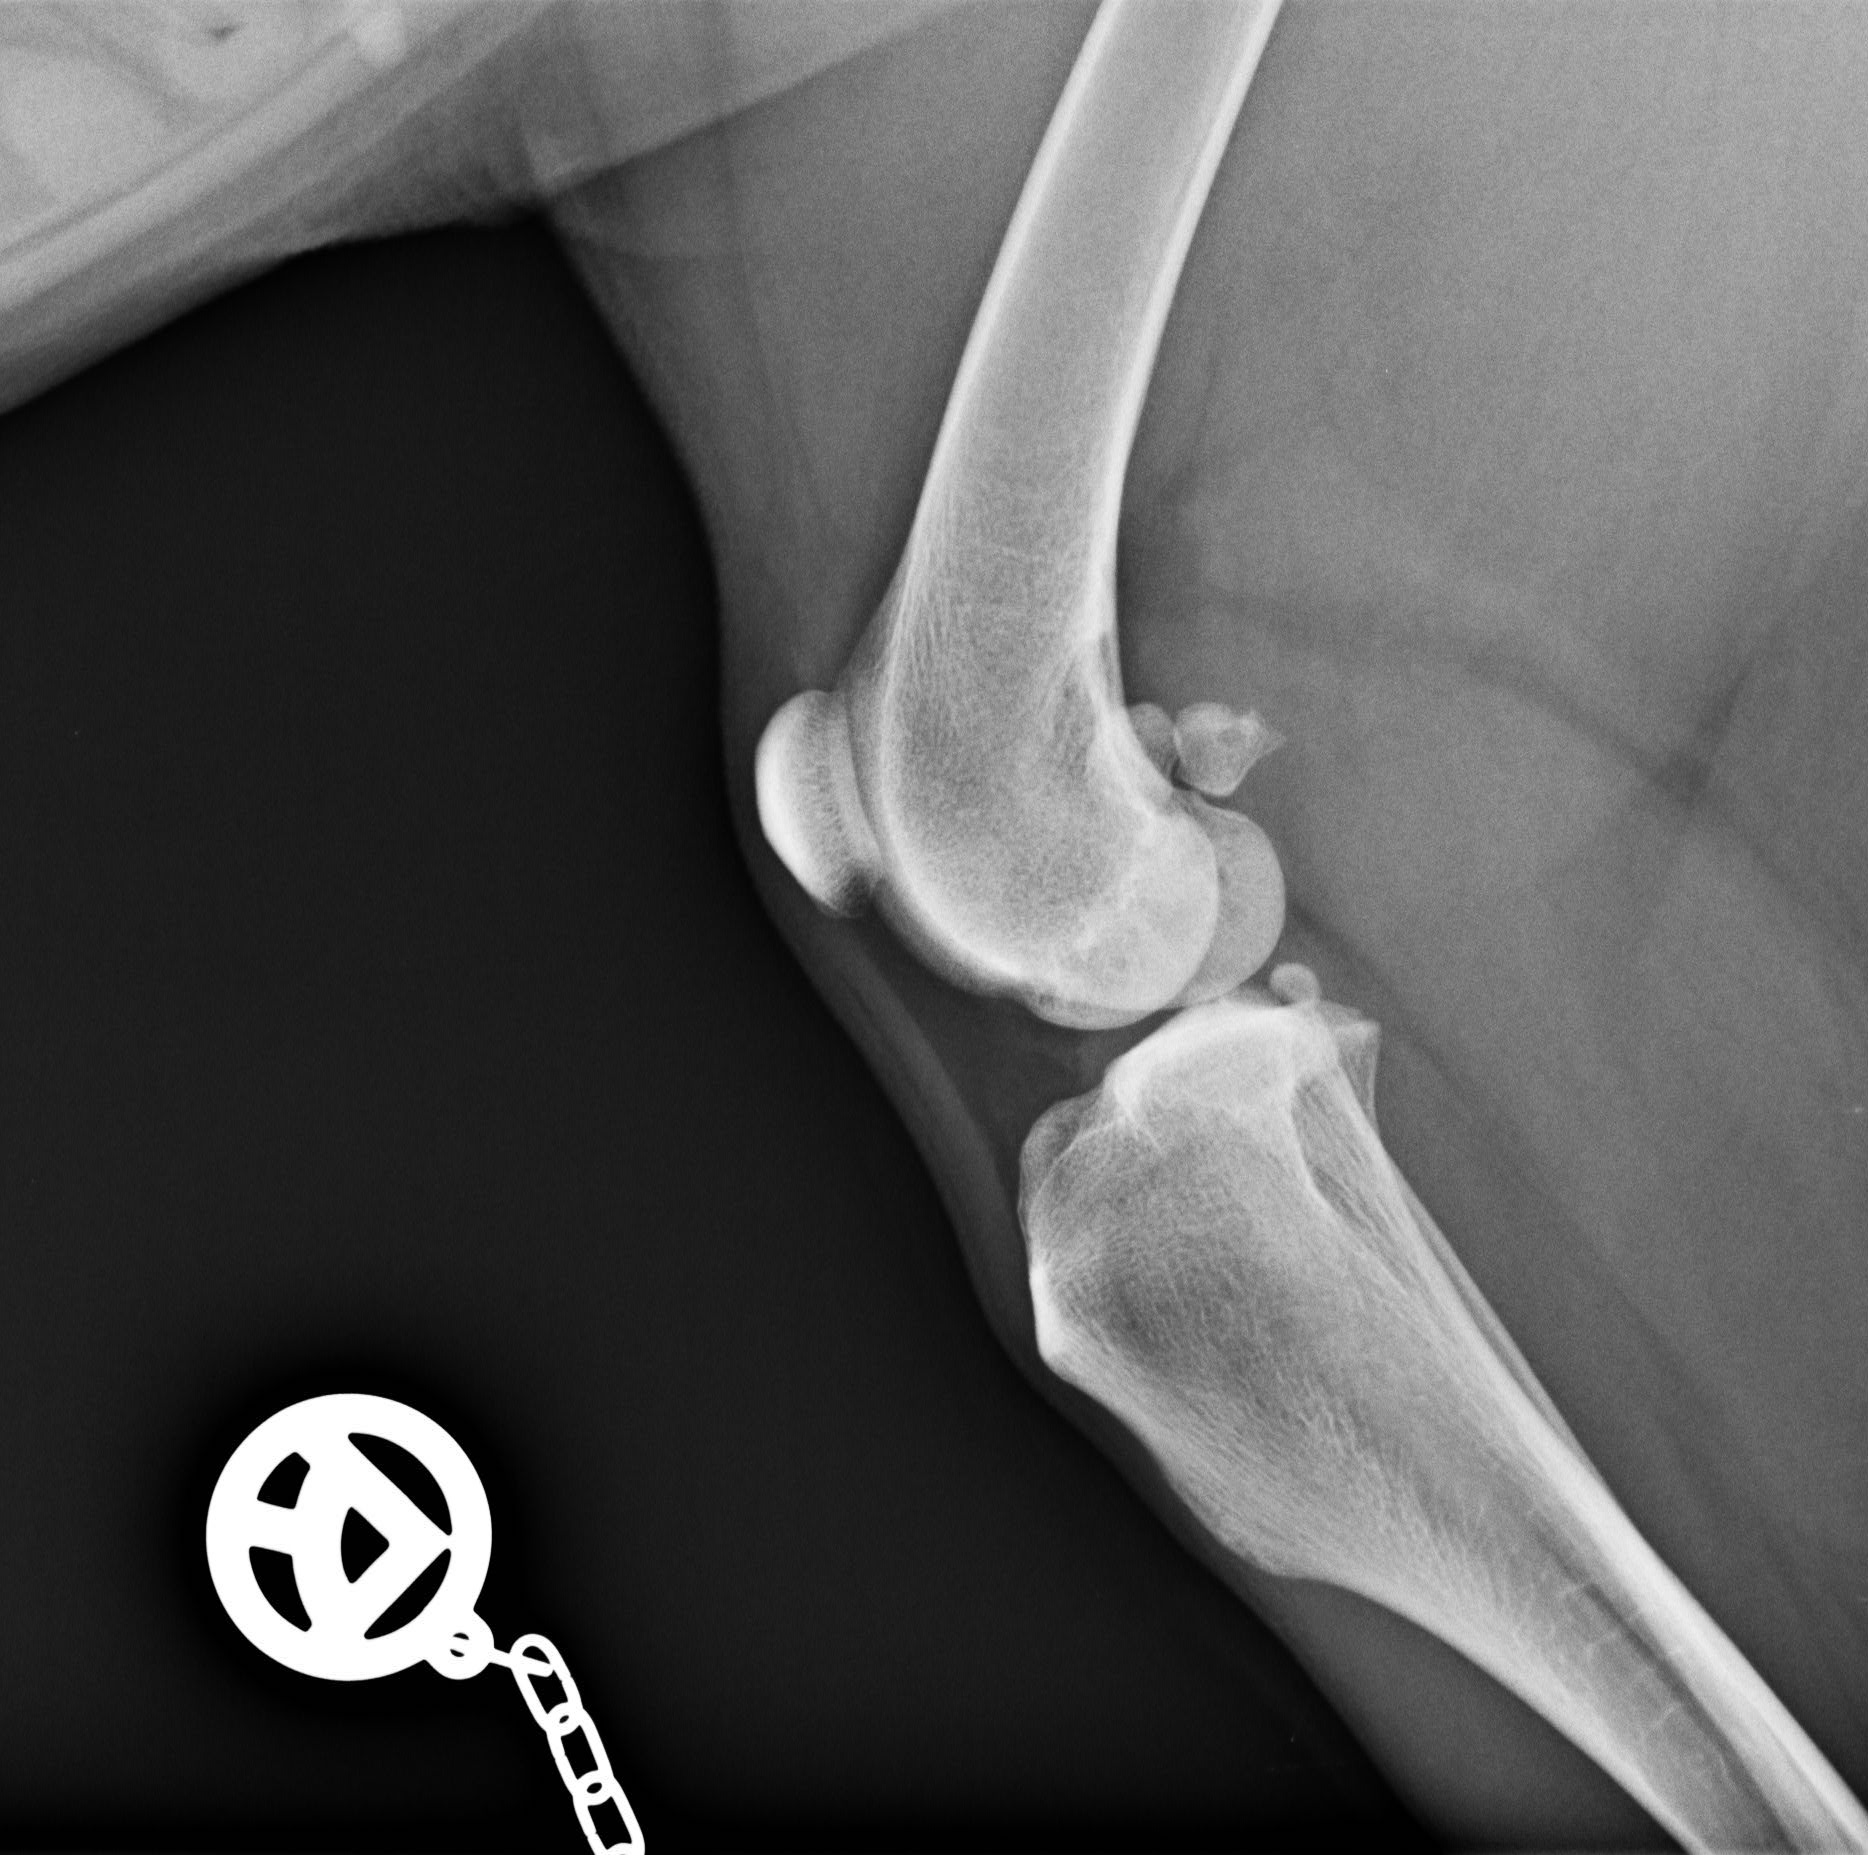

Manche Diagnosen lassen sich durch Röntgenbilder schnell und unkompliziert stellen. Dafür steht uns ein digitales Röntgengerät zur Verfügung, welches die Strahlenbelastung für Ihr Tier möglichst gering hält. Zur exakten Befundung des Zahnstatus steht uns ein dentales Röntgen zu Verfügung.

Digitales Röntgen